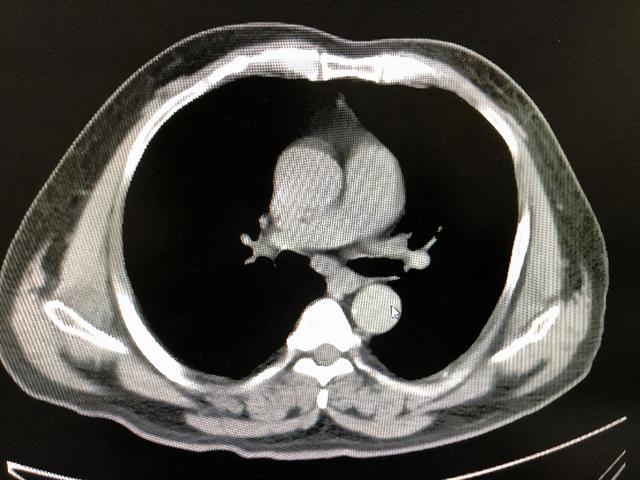

CT模拟定位